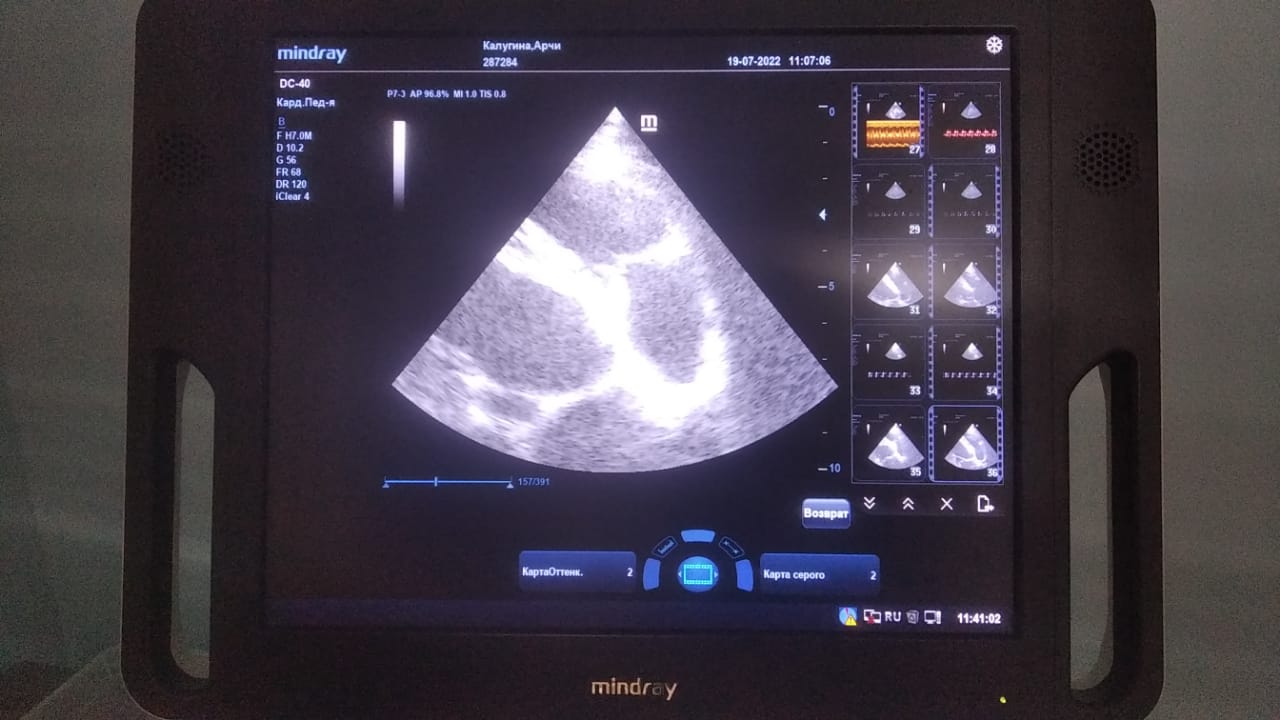

Анализы Арчи. Сердца и легких

Вложения

IMG-20220719-WA0100.jpg

IMG-20220719-WA0102.jpg

IMG-20220719-WA0104.jpg

IMG-20220719-WA0103.jpg

IMG-20220719-WA0105.jpg

Продолжение.